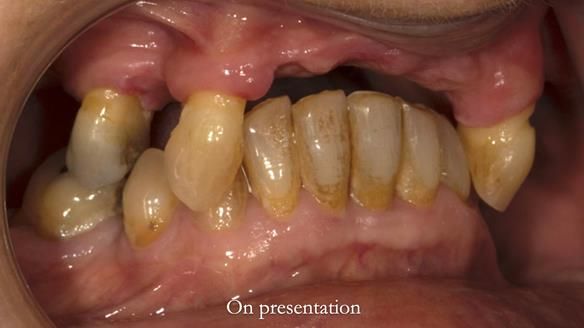

In this edition, I present the removable partial denture treatment for Jean, an 80-year-old woman with a sore mouth caused by a soft tissue-supported 'gum stripper' acrylic denture and a clenching habit. Below, I outline the step-by-step process of her treatment. It wasn't straightforward; I had to remake the denture after it fractured to achieve a satisfactory result. Each patient is unique, and sometimes a new RPD serves as a prototype. Occasionally, I need to make adjustments, learn from any mistakes, and refine the design to get it right.

The treatment has been a success over the past 4 years.